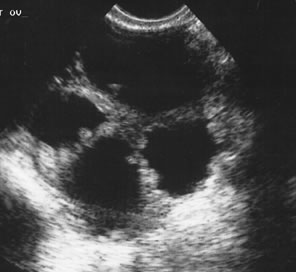

Fig. 3. A 3-dimensional study in a perimenopausal patient identified a multiloculated 3.5-cm cyst. Power Doppler examination was unremarkable. Surgery revealed a benign cystadenoma.